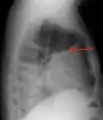

CT scan of the chest showing a left-sided pleural effusion. The fluid usually settles at the lowest space due to gravity; in this case, at the back because the patient is supine.- The lung expanding within an area of pleural effusion as seen by ultrasound

A pleural effusion as seen on lateral upright chest x-ray- Pleural effusion as seen behind the heart.[17]